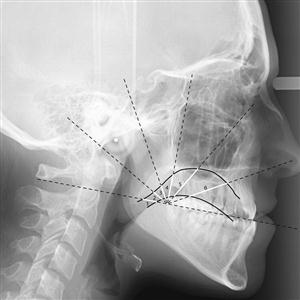

Digital Cephalogram = Digital Lateral X.Ray of Skull with Jaw / Mandible for treatment of uneven and protruded / mal-aligned teeth mainly prescribed by orthodontists. Usually required for young patients.